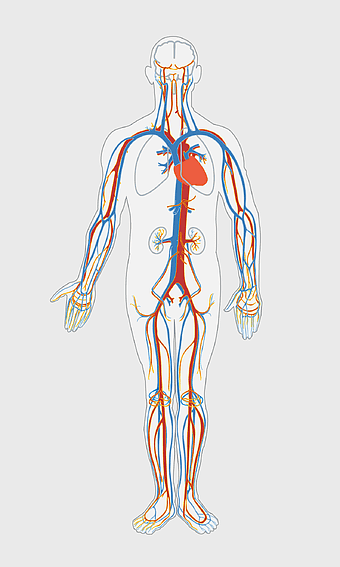

human circulatory system, blood vessel anatomy, weight loss exercise benefits, heart and artery health, vascular network visualization, cardiovascular health illustration, systemic circulation diagram -

heart anatomy illustration, cardiovascular system diagram, circulatory system medical, vascular system sonography, human body blood flow, arterial network visualization, heart function analysis -

circulatory system anatomy, omega-3 fatty acids benefits, cardiovascular health, medical illustration, human body vascular network, blood vessel visualization, heart function diagram -